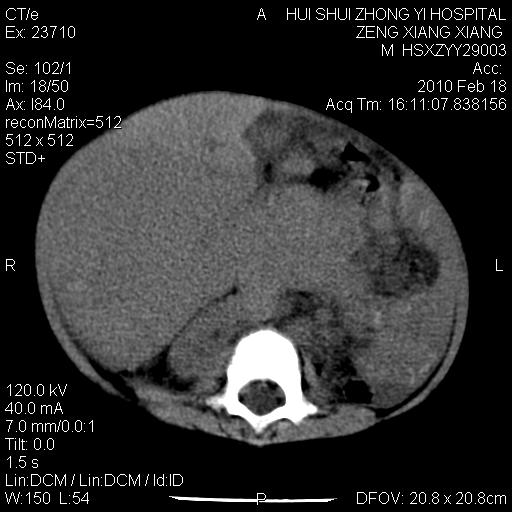

标题: PED3106:男,2岁,腹胀1月。 [打印本页]

标题: PED3106:男,2岁,腹胀1月。

定位腹膜后,肾上腺来源;

定性:恶性神经源性,肾上腺神经节母细胞瘤可能性大。

鉴别:肝母、肾母、肝脏中胚层错构瘤。

依据:年龄、有钙化,肾脏及肝脏受压移位。

肝母细胞瘤可能性大,右肾形态大体可见,不支持肾母细胞瘤,右肾移位不明显,肾上腺神经母细胞瘤可能性不大。